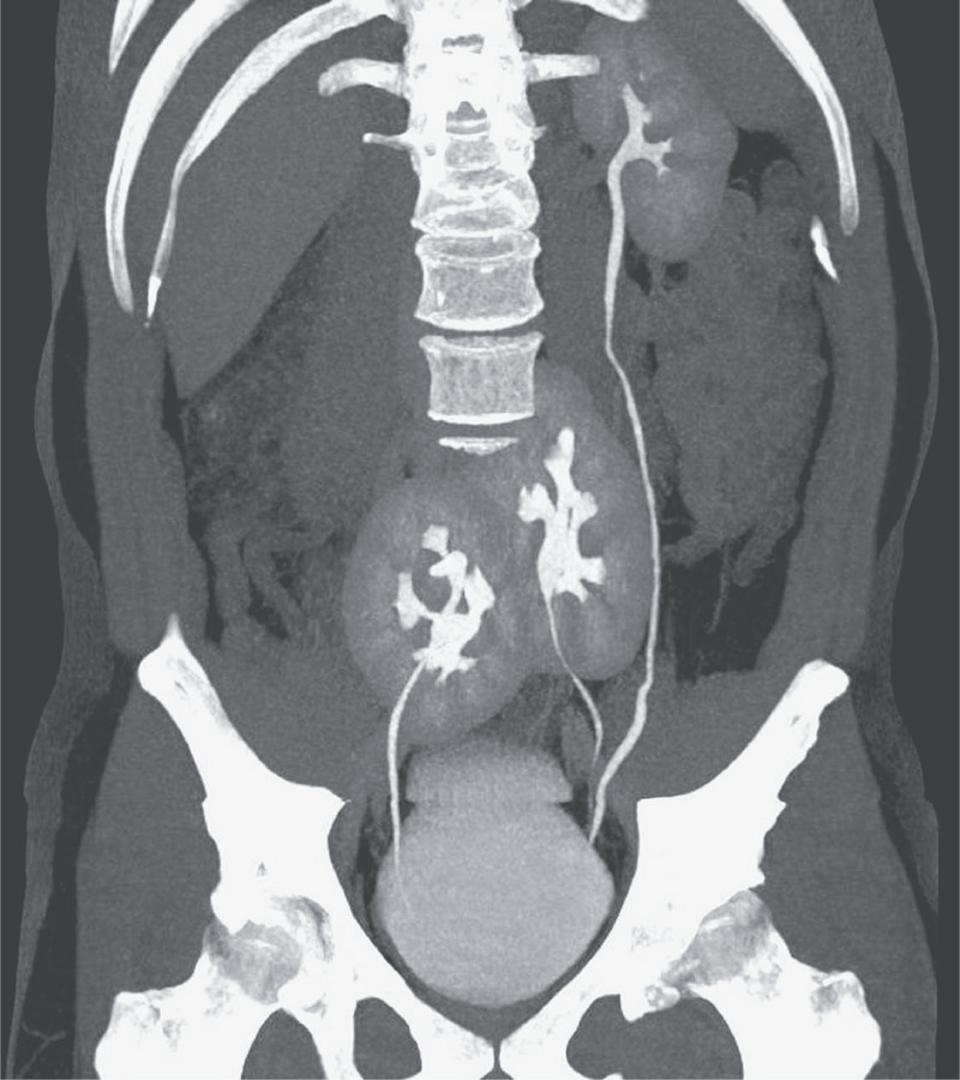

Zbog teških bolova u donjem dijelu leđa, liječnici su poslali 38-godišnjeg Brazilca na CT sken. Sken je otkrio uzrok boli - herniju diska, ali i prisutnost tri bubrega.

Liječnici iz bolnice Do Rim u Sao Paulu vidjeli su lijevi bubreg normalnog izgleda i dva spojena bubrega na području zdjelice, navodi se u članku objavljenom u uglednom medicinskom časopisu The New England Journal of Medicine.

Foto: nejm.org

Tri bubrega je relativno neobičajna pojava, navode stručnjaci i ističu kako je otkriće istih najčešće slučajno jer rijetko uzorkuje probleme. Smatra se kako se za to ni ne zna osim ako se ne napravi CT sken zbog nekog drugog zdravstvenog razloga, kao što je to bio slučaj s 38-godišnjim Brazilcem.